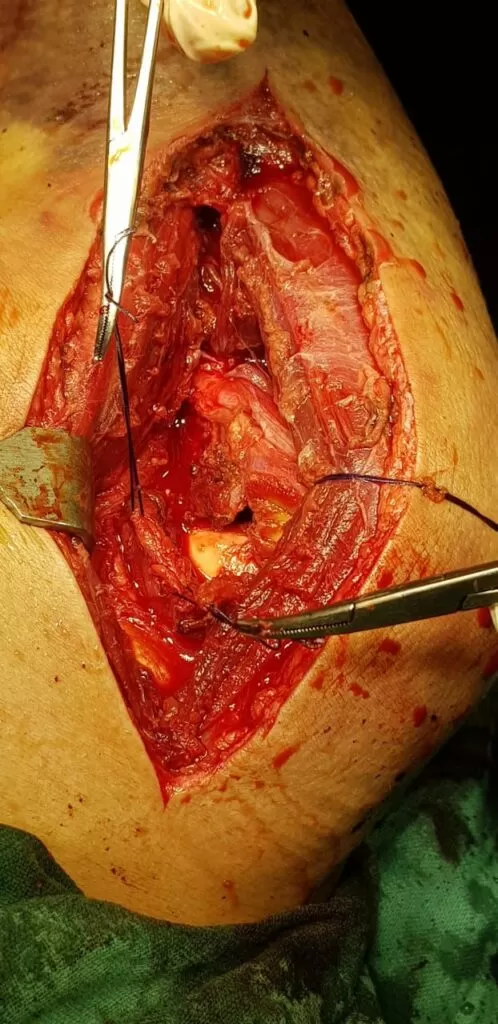

Mr. Akeel

Name: Mr. Akeel

Date of Operation: 10 Mar 2024

Age: 46 Years

Complex Trauma